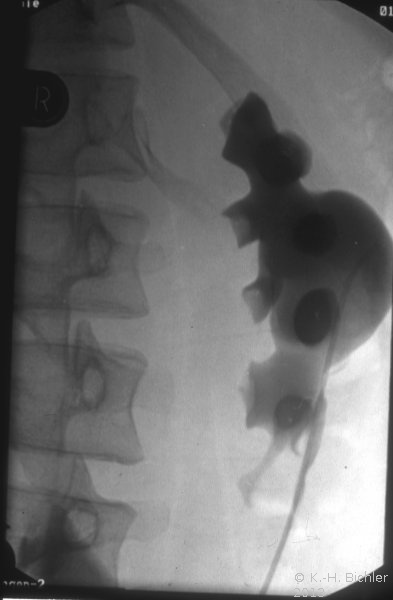

Die retrograde Sondierung gab Hinweis auf ein strangulierendes Hindernis im Bereich des Harnleiterabgangs (aberrierendes Gefäß, Bride?). Das retrograde Pyelogramm zeigte ein erweitertes, aber sonst unauffälliges NBKS (Abbildung 6).